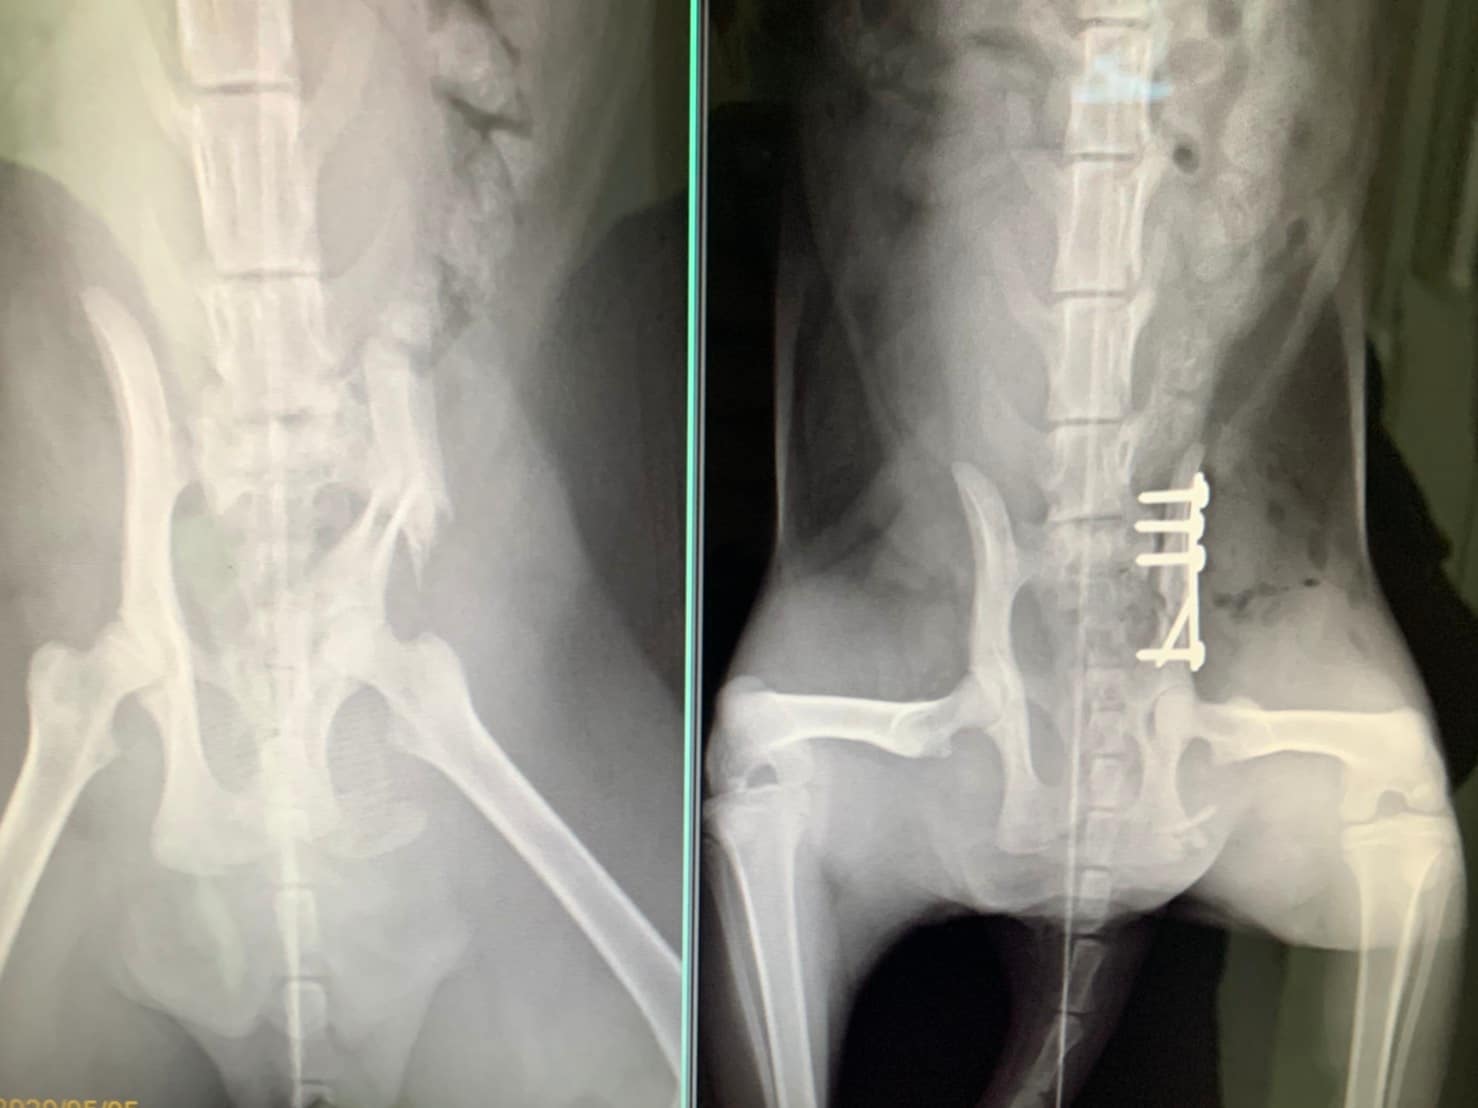

主題: 勞動節出車禍的咪咪 申請者姓名: 陳忠政 花色: 申請日期: 2020-05-07 18:48:19 申請者部落格: 申請者臉書網址: https://www.facebook.com/profile.php?id=100009508179964 所在縣市/合作醫院: 高雄市/恩澤動物醫院 治療費用: 29000元 需求人數: 65人 已結案 (2024-05-31 18:17:19) 報名人員: ivie(已付款)、郁婷(已付款)、Bymove Huang x2(已付款)、禪、河(已付款)、黃俊清 x2(已付款)、顏維成 x2(已付款)、雲荻(已付款)、樂爸(已付款)、Jube(已付款)、Joshua(已付款)、Irene Shen(已付款)、統粉 x4(已付款)、Patrick Yang x4、黃馬力、YUPEI(已付款)、叭噗呢 x2(已付款)、叭噗呢 x2(已付款)、Xtina(已付款)、JudyHsiao x2、Yuyu Yan(已付款)、黃丫丫 x2(已付款)、River Chen(已付款)、Catherine Tseng x2(已付款)、Jane Hong(已付款)、winz(已付款)、allyn(已付款)、pupu x2(已付款)、chiawei(已付款)、Doris(已付款)、涂咪咪(已付款)、Jerry Huang(已付款)、emmalin x2(已付款)、風中火(已付款)、Snow Su x3(已付款)、Rita x2(已付款)、晶晶(已付款)、Claire Li(已付款)、禪、罐頭(已付款)、Ryan(已付款)、Ikea x2(已付款)、御用鏟屎官(已付款)、JUN(已付款)、七品摌屎官(已付款)、Wwusong Chang(已付款)、solosos x2(已付款)、林宛瑾 x6(已付款)、 候補人員: 動物病情說明: 咪咪是我在勞動節發現的,當時正趕往醫院執行勤務,發現他趴在馬路中央,當下覺得很怪所以回頭看了一眼,發現一台車從他身上經過咪咪都沒動,趕緊移到路旁請友人幫忙送醫。

咪咪算幸運,當天晚上終於找到一家快休息的醫院,在ICU住了一晚,隔天移到湖光醫院做檢查,發現左側骨盆骨折、關節脫位、鼻部分有傷口,建議盡快轉院評估手術,5/4轉至恩澤醫院進行治療,經醫院評估後須做手術,不然日後排便會有問題。動物近況說明: 咪咪於5月6號已開完刀,目前狀況良好,也開始進食,目前住院觀察